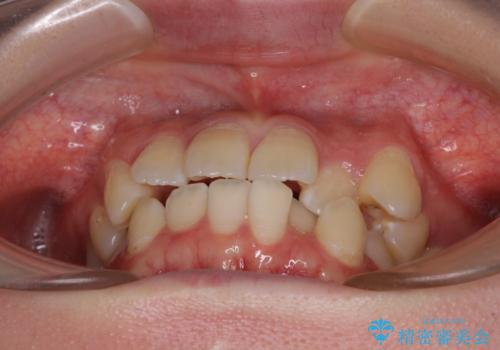

インビザラインでの治療を希望されていましたが、前歯のクロスバイトや下顎小臼歯の捻転が認められたため、インビザライン単独で治療を行うよりも、ワイヤー装置を併用した方が、治療期間の短縮やトラブル回避できると判断し、ワイヤー装置を併用することとしました。

まずはワイヤー装置により前歯のクロスバイトと下顎小臼歯の捻転を改善し、その後インビザラインにより全体を整える矯正治療を行うこととしました。

前歯のクロスバイトは、インビザラインでの改善中に前歯に過剰な力がかかり、歯髄壊死や歯肉退縮を引き起こすことがあります。また下顎小臼歯は寸胴型のため、捻転を排除することが難しいことが知られています。

それをワイヤー装置にて速やかに改善することで、トータルでの治療期間を短くすることができます。